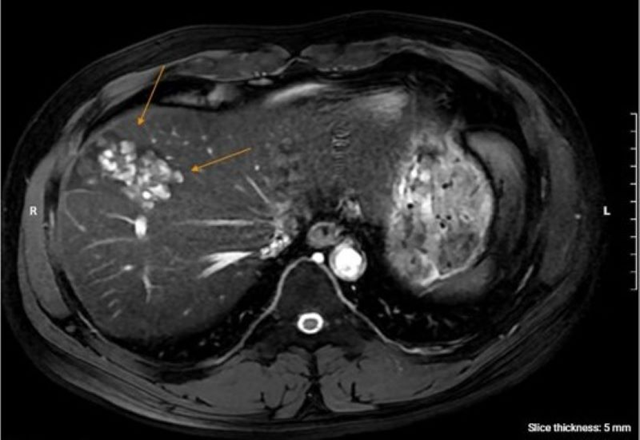

Kết quả xét nghiệm và chẩn đoán hình ảnh cho thấy anh dương tính với sán lá gan lớn và giun đũa chó mèo. Đồng thời, bác sĩ phát hiện một ổ áp xe gan kích thước gần 5 cm, kèm tăng chỉ số viêm và bạch cầu ái toan. “ Ổ áp xe khá lớn, nếu đến muộn có thể vỡ và gây nhiễm khuẩn huyết ”, bác sĩ Hương nhận định.

Bệnh nhân được điều trị bằng phác đồ gồm chọc hút ổ áp xe, thuốc diệt ký sinh trùng, kháng sinh và theo dõi liên tục các chỉ số viêm, men gan. Sau thời gian điều trị nội trú và theo dõi ngoại trú, bạch cầu ái toan trở về bình thường, ổ áp xe thu nhỏ và không còn dịch mủ. Triệu chứng sốt, đau hạ sườn và ngứa giảm rõ rệt, sức khỏe bệnh nhân hiện đã ổn định.